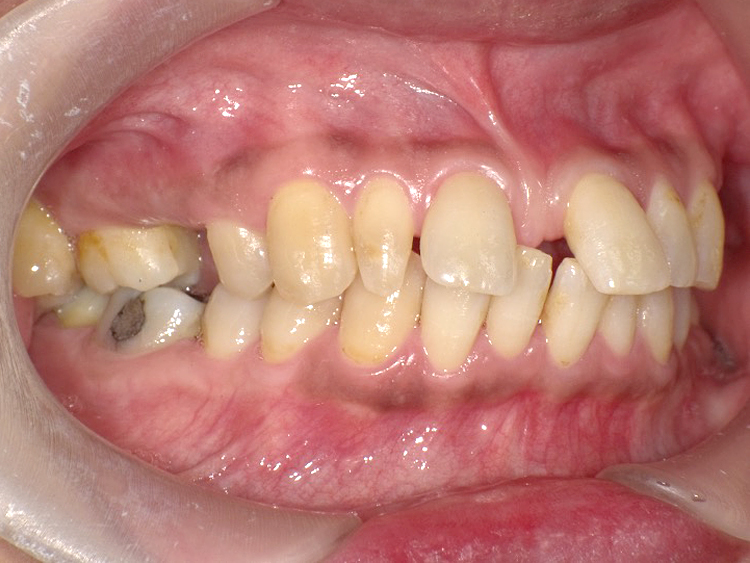

症例4

Before

After

| 主訴 | 上下前歯のがたつき |

|---|---|

| 年齢 | --- |

| 治療 期間 |

約9ヶ月 |

| 治療 内容 |

インビザラインiGoで上下顎の治療。 |

| 治療費 | ¥550,000(税込)/調整料含む |

| 治療のリスク | 矯正終了後は、リテーナーを指示通りに使用し、歯の後戻りを防ぐ必要があります。 |